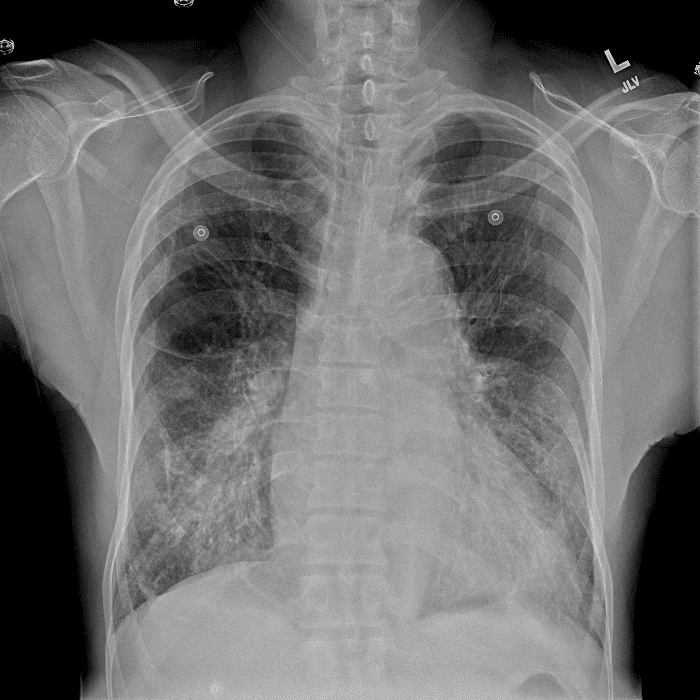

Practice Cases